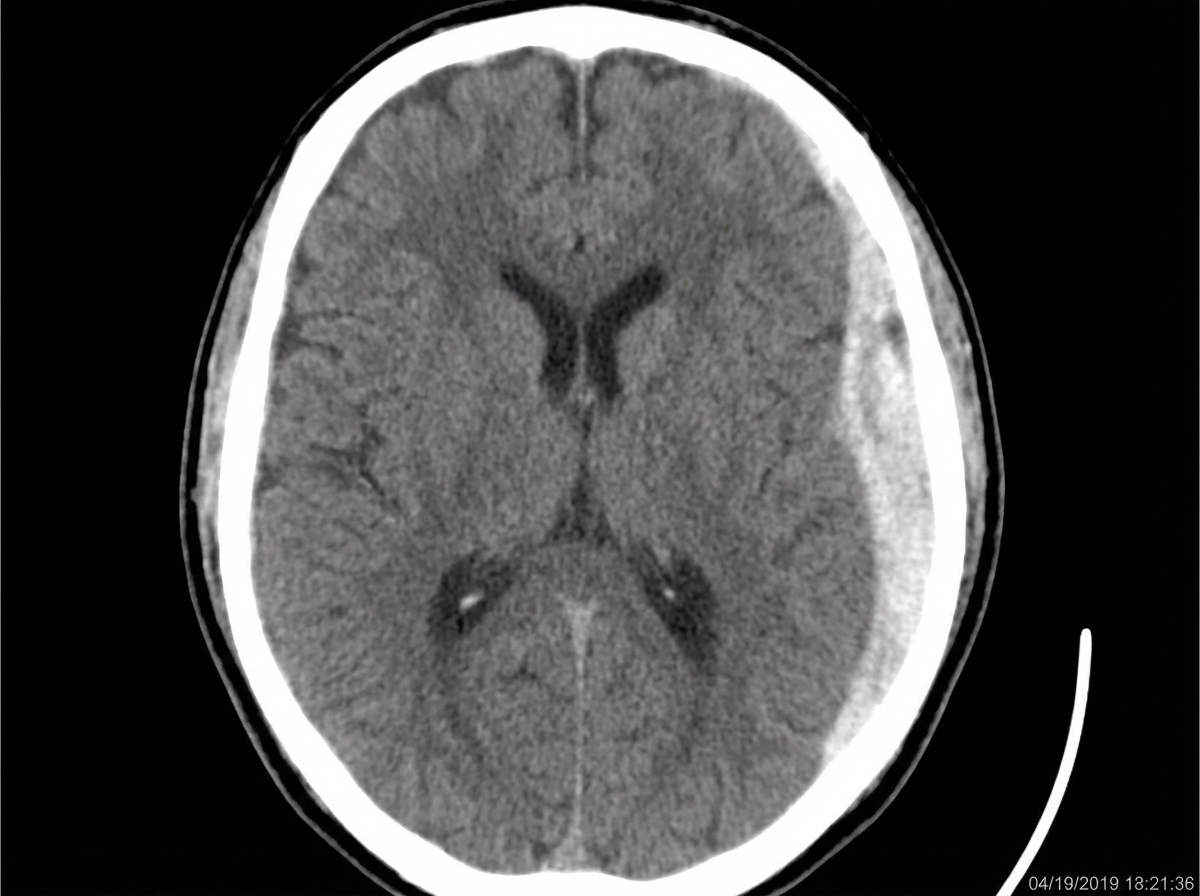

A 68-year-old community-dwelling woman is transported to the emergency department with decreased consciousness, headache, and nausea. The symptoms began after the patient had a syncopal episode and fell at her home. She has a history of arterial hypertension and atrial fibrillation. Her current medications include hydrochlorothiazide, lisinopril, metoprolol, and warfarin. On admission, her blood pressure is 140/90 mm Hg, heart rate is 83/min and irregular, respiratory rate is 12/min, and temperature is 36.8°C (98.4°F). She is conscious and verbally responsive, albeit confused. She is able to follow motor commands. Her pupils are round, equal, and poorly reactive to light. She is unable to abduct both eyes on an eye movement examination. She has decreased strength and increased tone (Ashworth 1/4) and reflexes (3+) in her right upper and lower extremities. Her lungs are clear to auscultation. The cardiac examination shows the presence of S3 and a pulse deficit. A head CT scan is shown in the picture. Which of the following led to the patient’s condition?